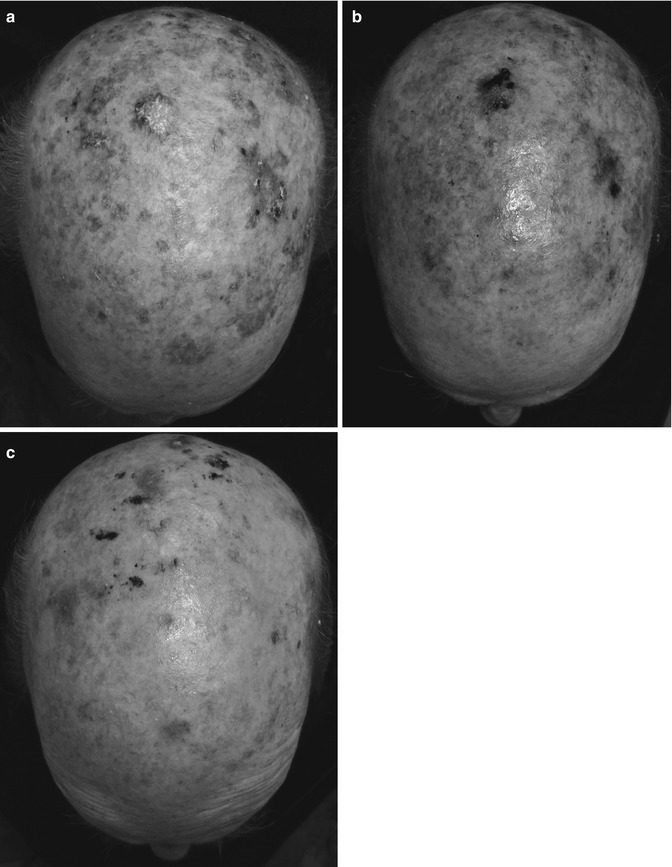

Cryopeeling on sun-damaged area on the occipital area of the scull (a) before, (b) 3 months, and (c) 9 months after treatment

Same patient as in Fig. 16.7 with image processing (infrared) which (a) allows assessment of the extent of the damage (redness is seen as black; keratin is seen as white); (b) 3 months post treatment; (c) 9 months after treatment with almost no black lesions (hypervascularization)